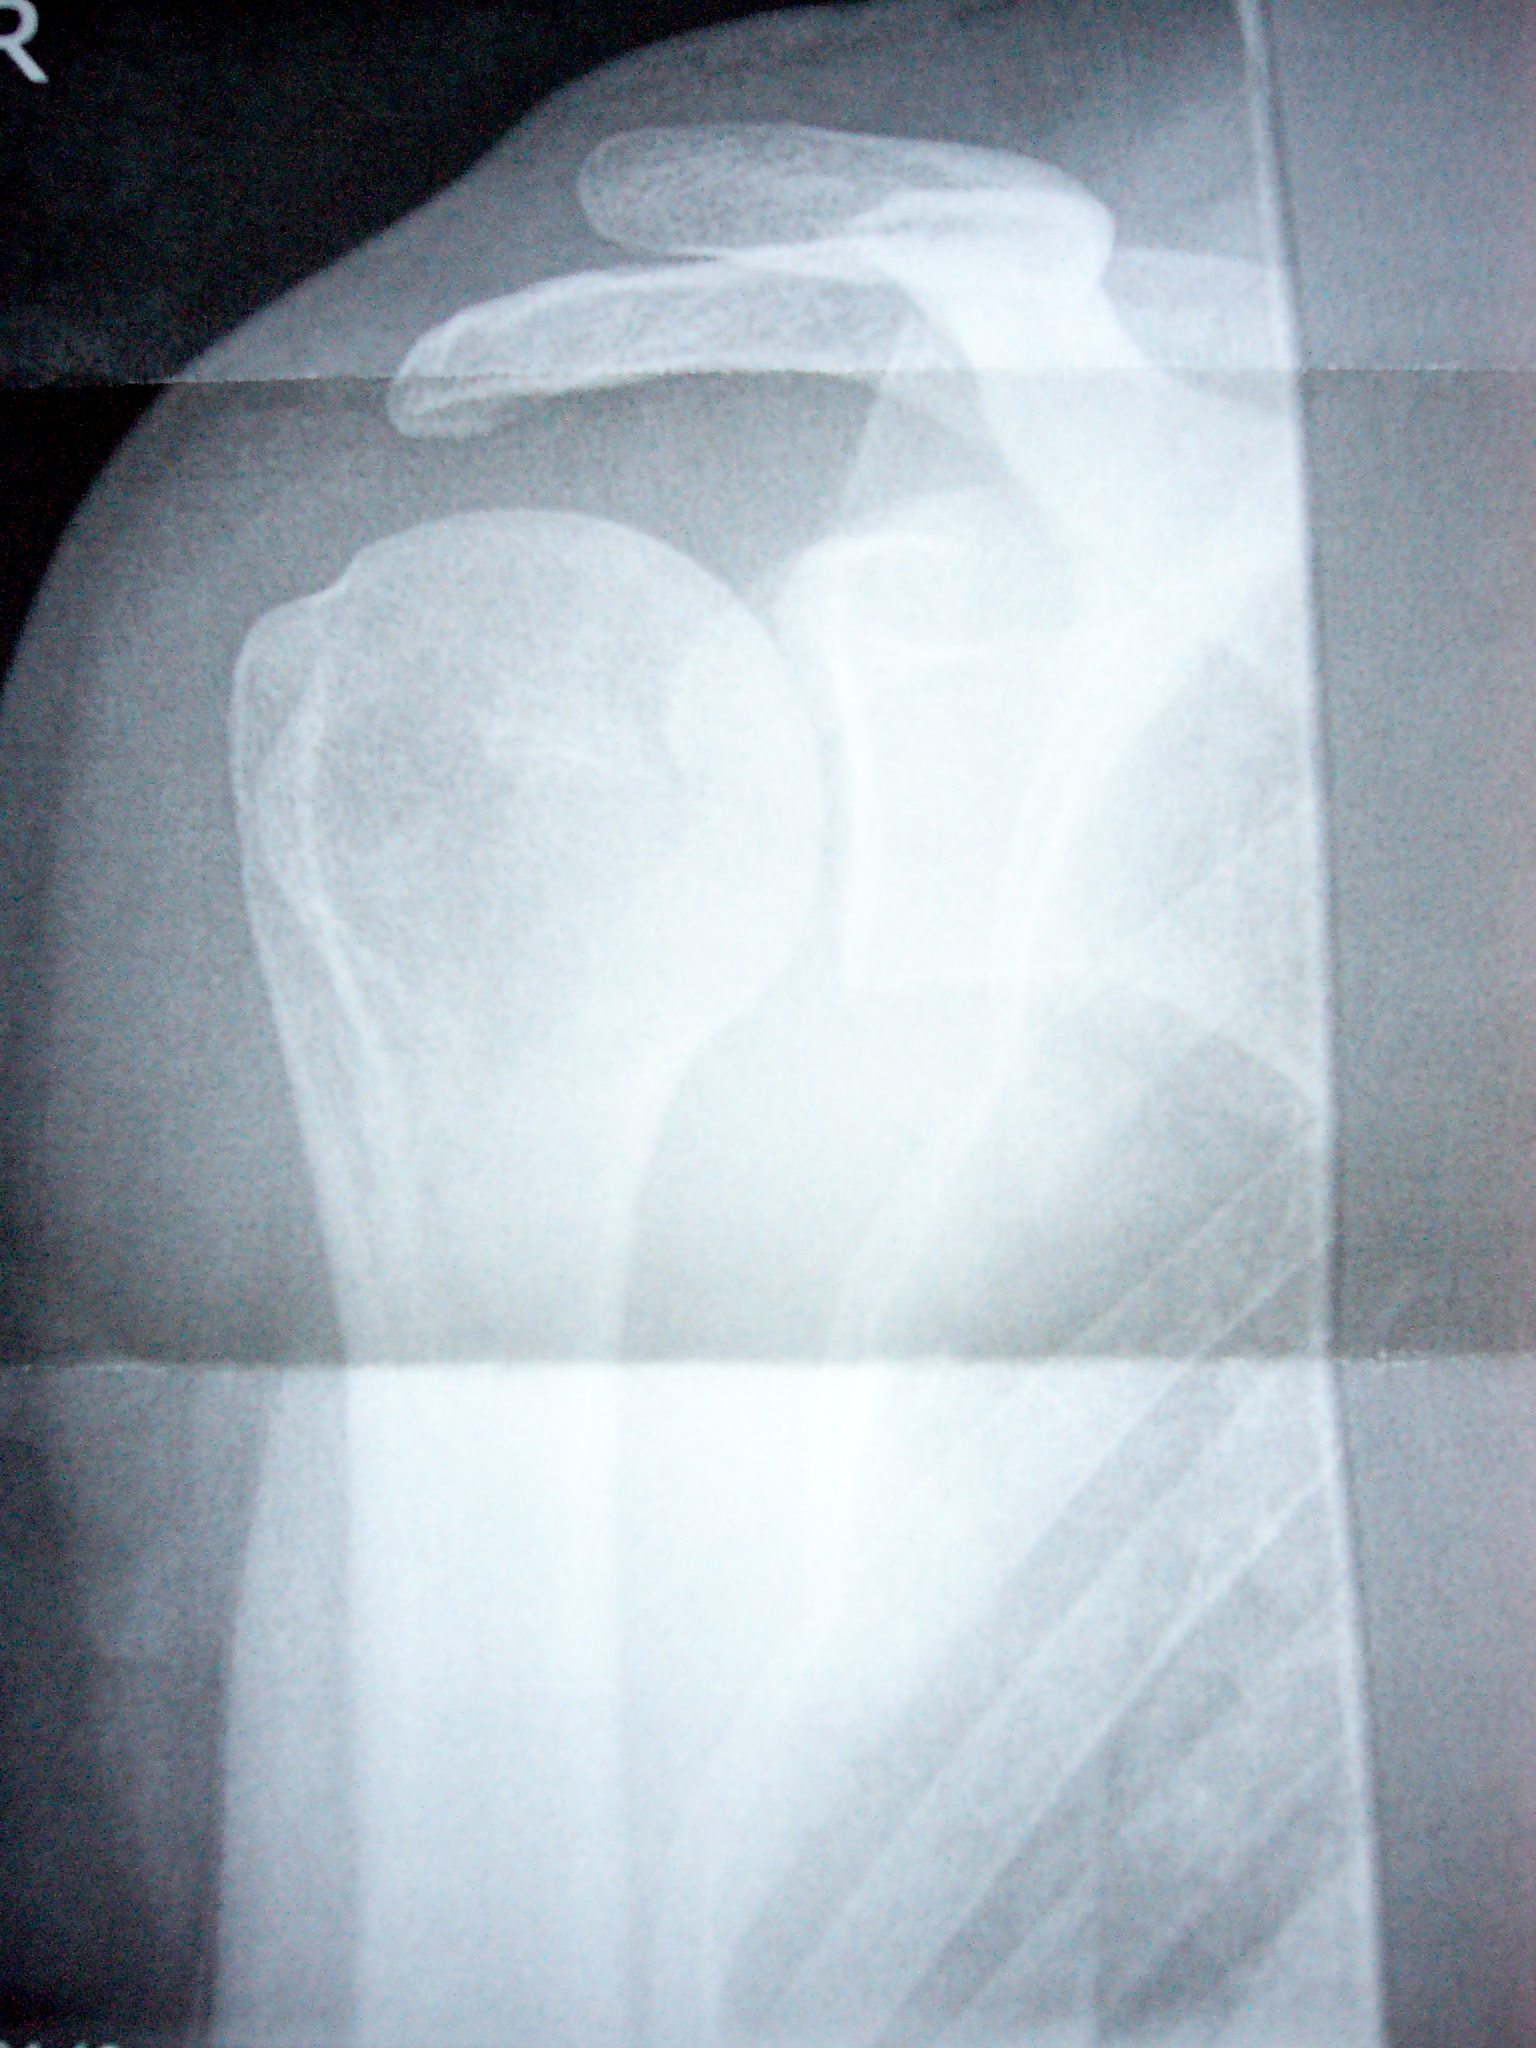

und...jetzt hat der arzt mir den zettel weggenommen, wo das draufstand. ac-sprengung auf jeden fall. das heisst, dass da. wo der oberarm oben mit dem schulterblatt und dem schlüsselbein verbunden ist, da ist es abgerissen. und nunist da ein grosser spalt, wo keiner sein sollte. sihe das schöne bild. der knochen, der da so nach oben ragt, der soll wohl mehr so weiter unten sein. und nicht oben rausgucken.

L1030363.JPG

L1030363.JPG [ 1017.16 KiB | 3632-mal betrachtet ]